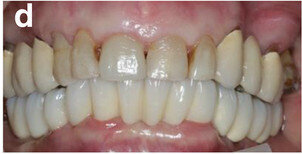

Fig. 14a: Occlusal, frontal and lateral views on the day of delivery, showing healthy peri-implant mucosal conditions (a) and the final CAD/CAM restoration in situ (b–e).

Fig. 14b: Occlusal, frontal and lateral views on the day of delivery, showing healthy peri-implant mucosal conditions (a) and the final CAD/CAM restoration in situ (b–e).

Fig. 14c: Occlusal, frontal and lateral views on the day of delivery, showing healthy peri-implant mucosal conditions (a) and the final CAD/CAM restoration in situ (b–e).

Fig. 14d: Occlusal, frontal and lateral views on the day of delivery, showing healthy peri-implant mucosal conditions (a) and the final CAD/CAM restoration in situ (b–e).

Fig. 14e: Occlusal, frontal and lateral views on the day of delivery, showing healthy peri-implant mucosal conditions (a) and the final CAD/CAM restoration in situ (b–e).

All six implants osseointegrated successfully without complications. After six months of the patient wearing the provisional FDP, a conventional impression was taken (screw-retained impression copings, open-tray technique, polyether material) to fabricate the final FDP on a new, precise cast (Fig. 11), which was then digitised with a laboratory scanner (Deluxe scanner, Open Technologies). The final framework was designed with straight connection to the implant platforms and with a cutback allowing for the veneering material (Figs. 12a & b). While the cobalt– chromium framework was fabricated using CAD/CAM technology (exocad, exocad; M1 Wet, Zirkonzahn), the veneering was performed manually, allowing for individual characterisation of the teeth (Figs. 13a–d). The models were fabricated with a laser stereolithography printer (XFAB) using an ABS-like polymer (Precisa RD096B, DWS). Healthy mucosal conditions were present at the delivery of the final CAD/CAM restoration, made from cobalt–chromium and composite veneering material (Figs. 14a–e). The accurately fitting FDP was attached with screws at 25 Ncm and the screw access area covered with composite material. The panoramic radiograph on the day of delivery showed optimal prosthetic and osseous conditions (Fig. 15). The patient followed a regular maintenance programme at the dental hygienist twice a year.